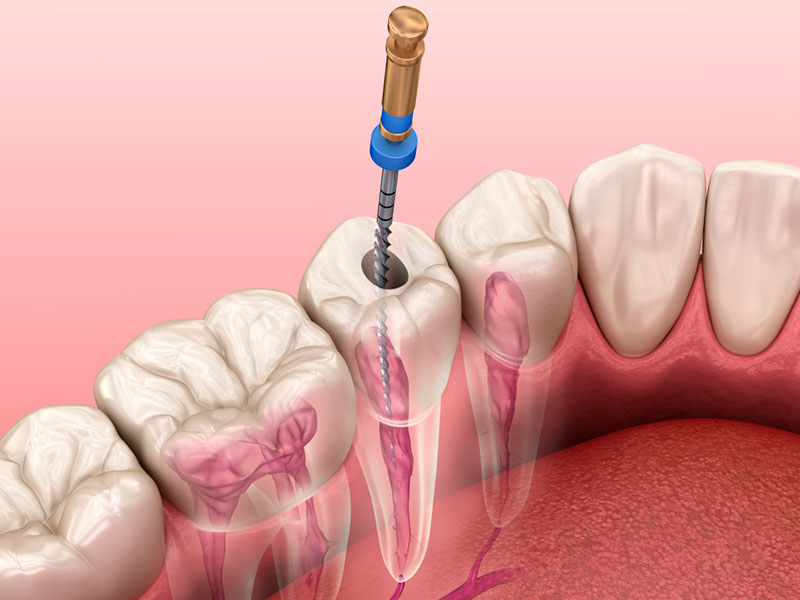

Usamos limas específicas que alargam os canais radiculares até 0,06mm de diâmetro.

Limpeza e Modelagem Interna: Com o dente anestesiado, o profissional acessa a câmara pulpar. Ferramentas finíssimas, as limas endodônticas, entram em ação para remover todo o tecido inflamado ou infectado. Elas também ajudam a alargar e modelar os canais radiculares, preparando o terreno para a desinfecção.

Desinfecção Profunda: A higiene interna é crucial. Soluções irrigadoras, como o hipoclorito de sódio, são usadas para lavar e desinfetar os canais, eliminando bactérias e garantindo um ambiente limpo. Esse passo é um dos mais importantes para o sucesso do tratamento.

O Processo de Limpeza: O dentista utiliza instrumentos específicos para limpar e desinfetar os canais radiculares. A remoção do tecido doente e a desinfecção são etapas cruciais para eliminar a infecção e prevenir problemas futuros. É um trabalho minucioso de higienização interna.

Irrigação Inteligente: A irrigação contínua durante o preparo do canal garante que a solução desinfetante alcance todas as áreas. Técnicas modernas e instrumentos ultrassônicos potencializam a ação desses líquidos, garantindo uma limpeza profunda e completa.